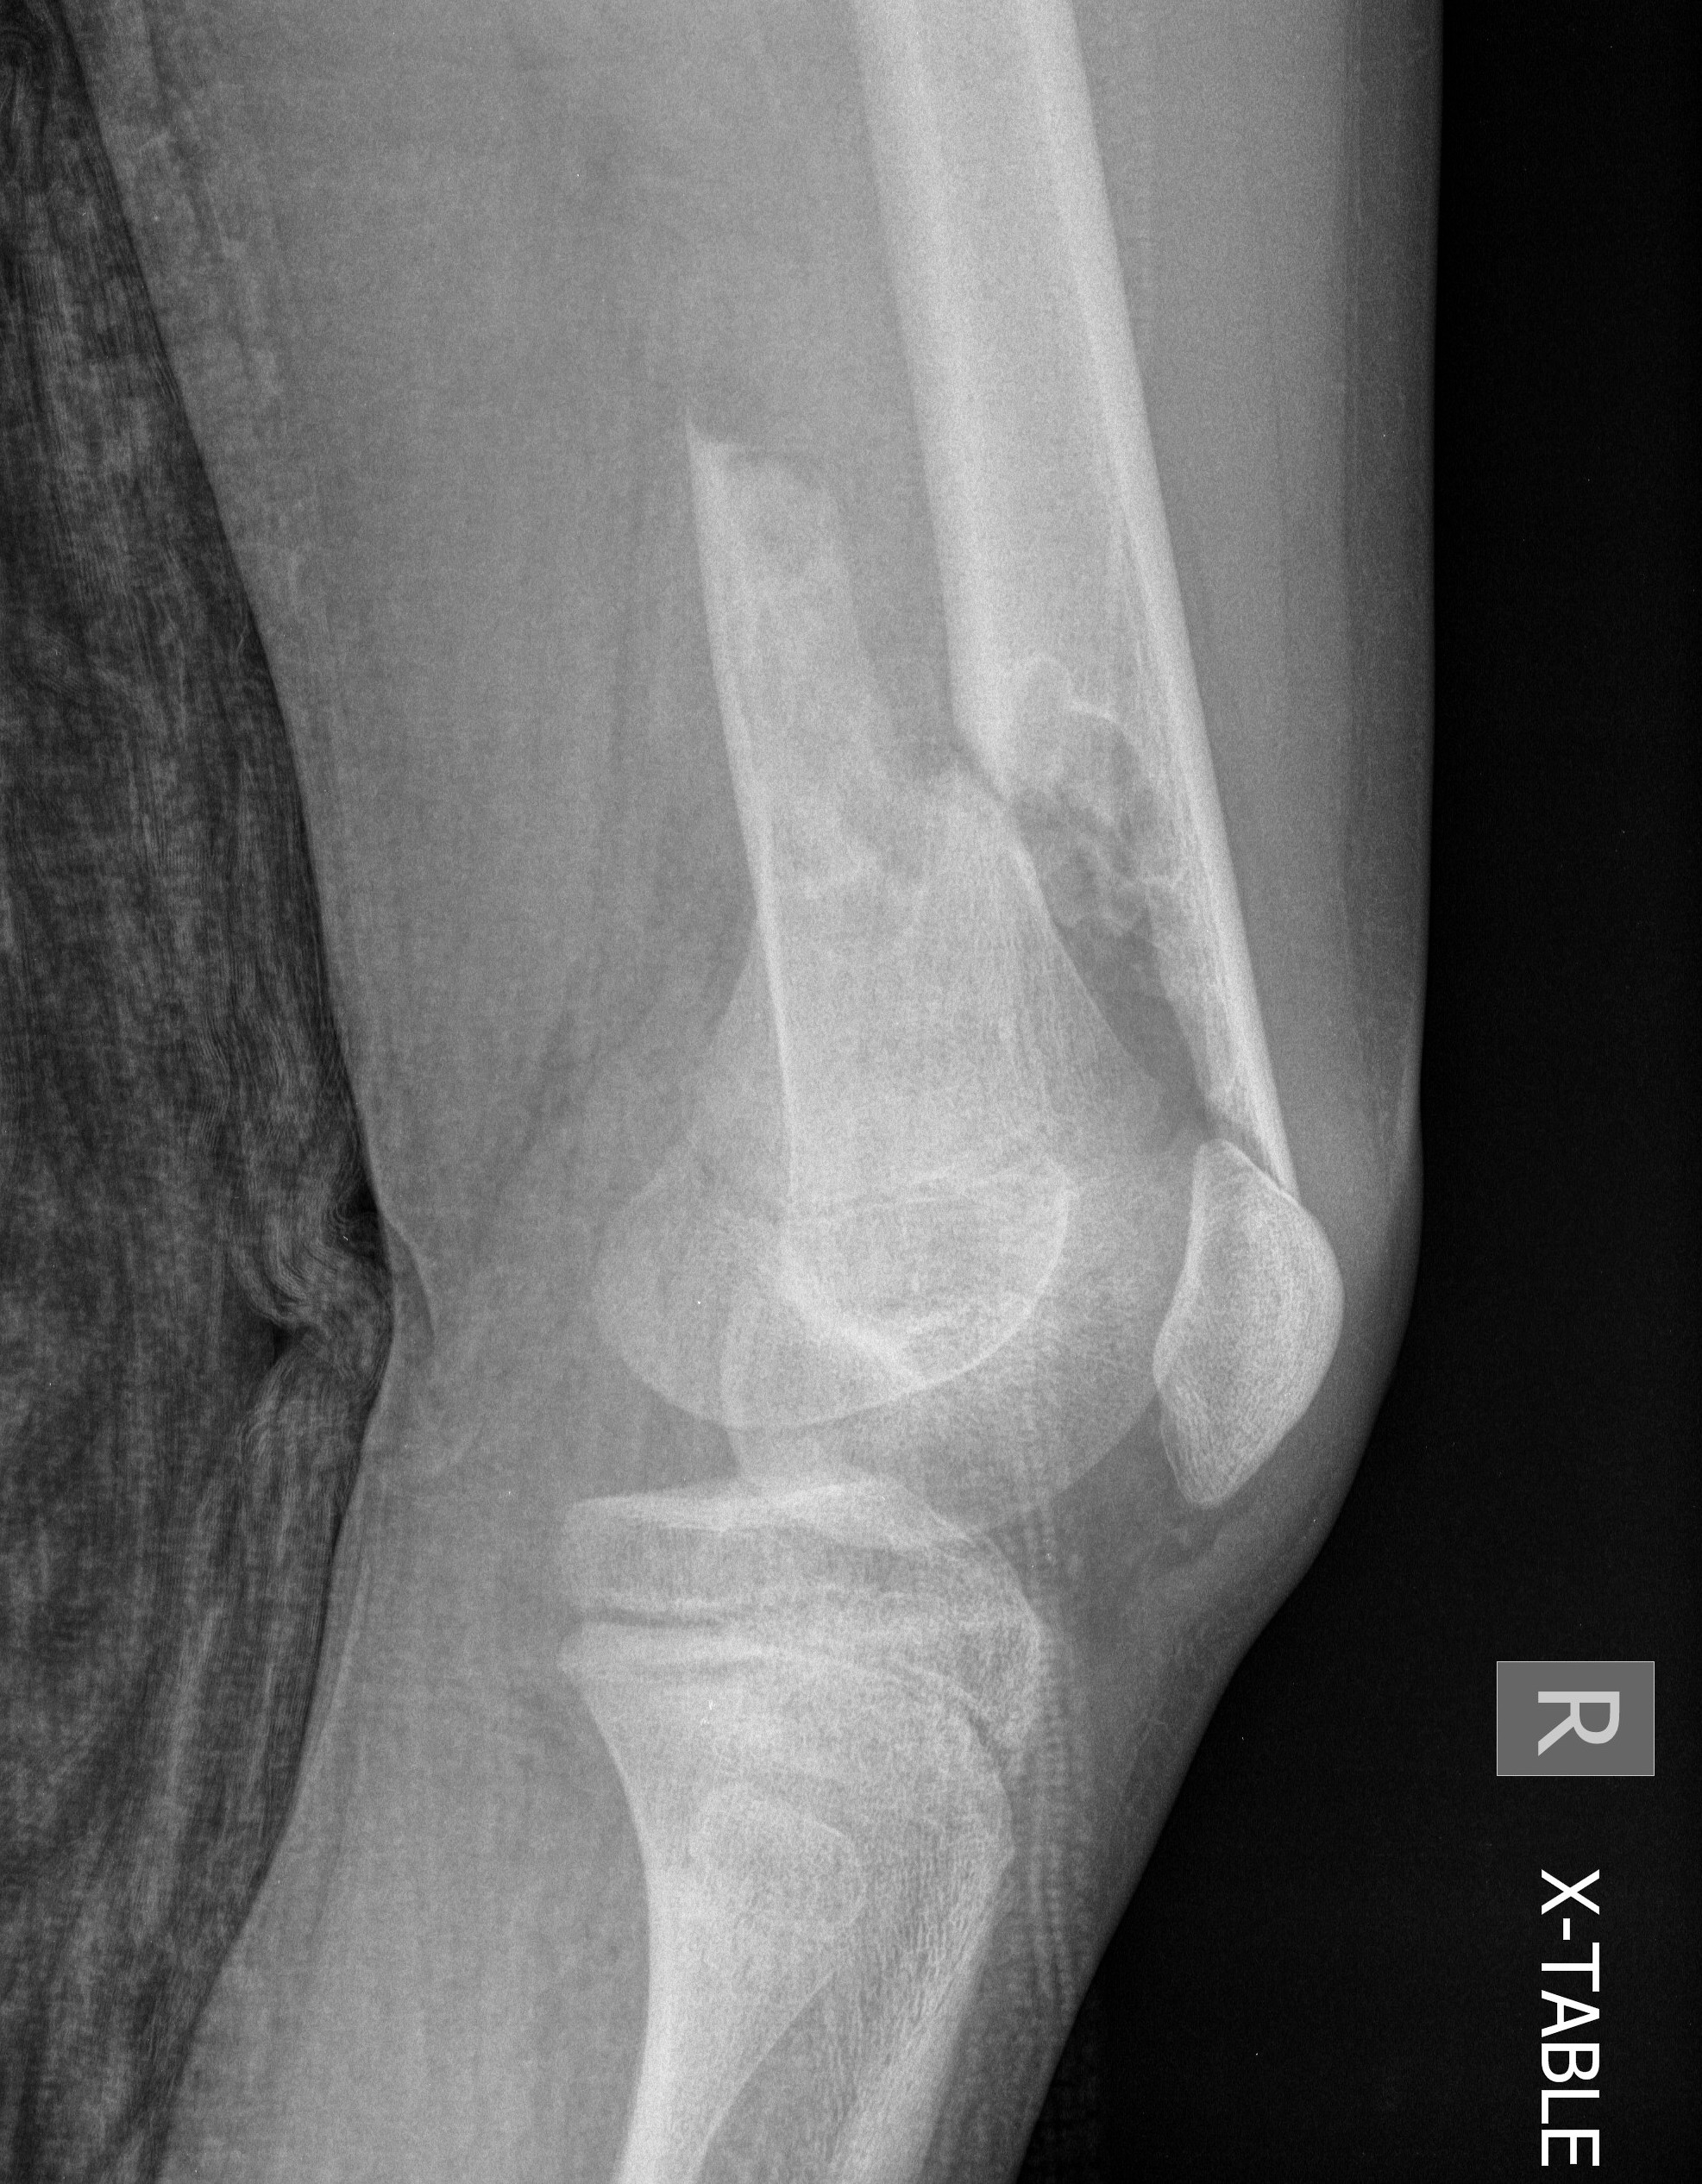

Salter Harris Type II with large Thurston Holland fragement

Distal Femur Salter Harris 2Distal Femur Salter Harris 2

Reduction

- attempt closed

- may be periosteum blocked on tension / medial side

Medial subvastus approach to knee

- identify Thurston-Holland fragment

- physeal sparing metaphyseal screws

Distal Femur SH2 ORIFDistal Femur SH2 ORIFDistal Femur SH2 Lateral